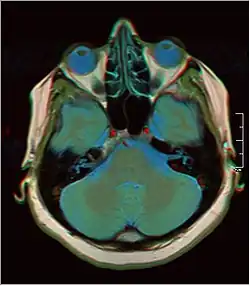

False color MRI by applying red to T1, green to PD and blue to T2.